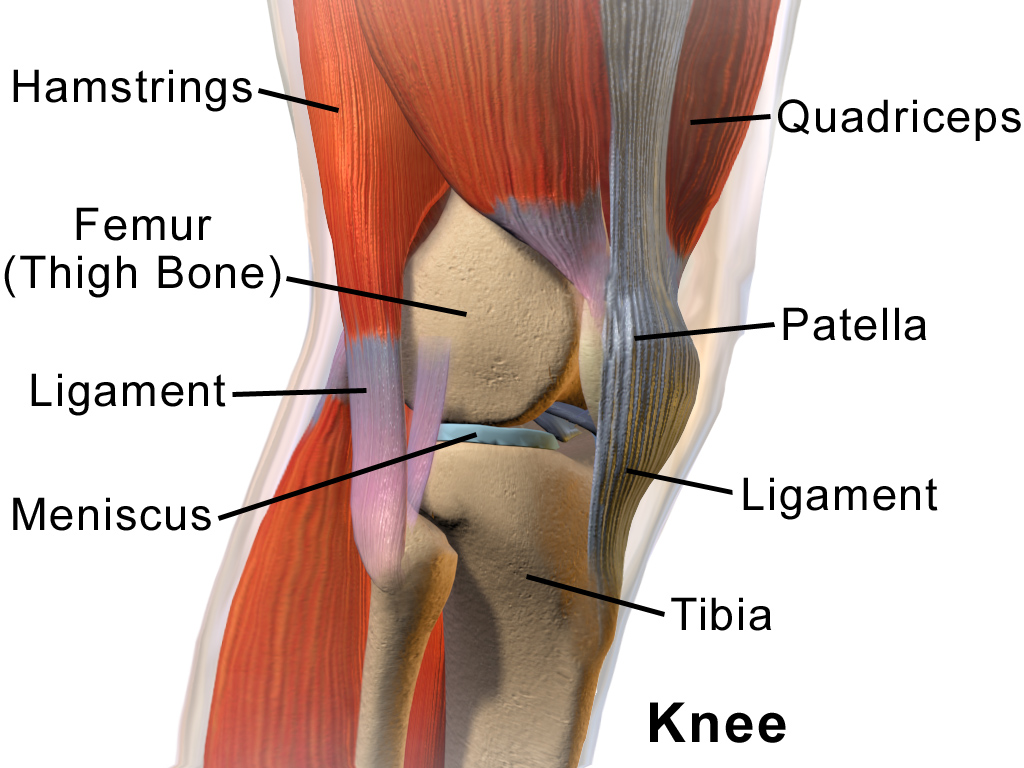

Η επιγονατίδα (patella ή kneecap) είναι ένα οστό το οποίο βρίσκεται στην πρόσθια επιφάνεια του γόνατος και συμμετέχει στις κινήσεις κάμψης και έκτασης της άρθρωσης. Είναι το μεγαλύτερο σησαμοειδές οστό (περικλείεται δηλαδή σε τένοντα) του ανθρωπίνου σώματος και συμμετέχει στον εκτατικό μηχανισμό του γόνατος.

Η επιγονατίδα φυσιολογικά κινείται προς τα κάτω και πάνω κατά την κίνηση κάμψης και έκτασης του γόνατος αυξάνοντας τον μοχλοβραχίονα για να επιτευχθεί αυτή ή κίνηση. Ακολουθεί την πορεία της μηριαίας τροχιλίας, μιας αύλακας δηλαδή στην πρόσθια επιφάνεια του μηρού, σχηματίζοντας την επιγονατιδομηριαία άρθρωση.

Συνδέει τον τένοντα του τετρακεφάλου προς τα άνω με τον επιγονατιδικό τένοντα που καταλήγει προς τα κάτω στην κνήμη.

- Οι πλάγιοι καθεκτικοί σύνδεσμοι που συγκρατούν την επιγονατίδα εντός θέσης και παίζουν το ρόλο στατικών σταθεροποιητών.

- Οι μύες πέριξ του γόνατος που ανήκουν στους δυναμικούς σταθεροποιητές.